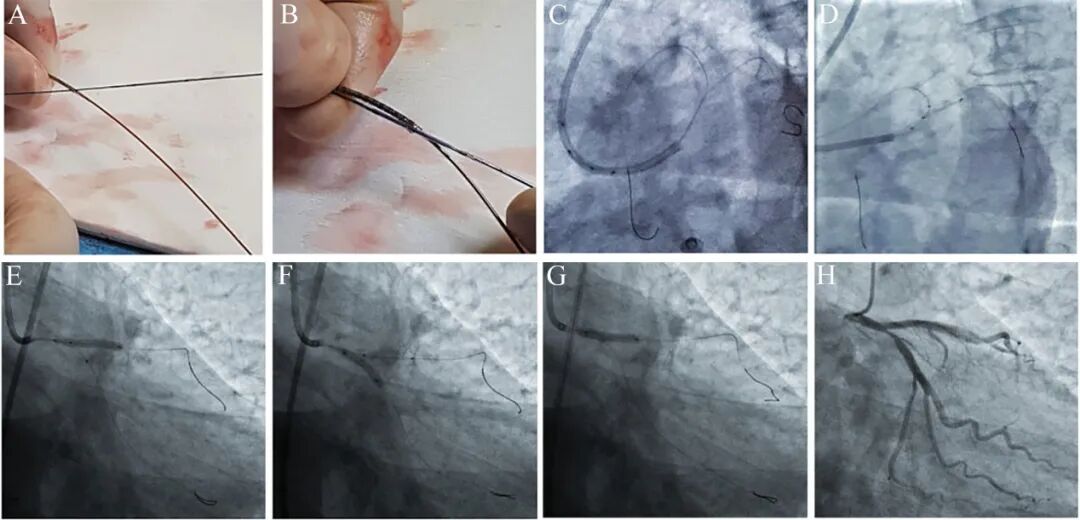

图6前降支开口花瓣技术[4]。

7FJL3.5指引导管,3.0×18 mm支架, 3.0×15mmNC锚定球囊。体外直接用锚定导丝硬头穿越尾端支架网孔(A),沿锚定导丝送入锚定球囊,支架和球囊的近端标志点对齐,用手捏紧支架整形(B)。支架球囊复合体送入体内(C),直至前三叉(D)。先前降支支架释放(E),然后回旋支锚定球囊扩张(F),最后支架球囊再次扩张(G)。造影发现回旋支开口受影响(H)。